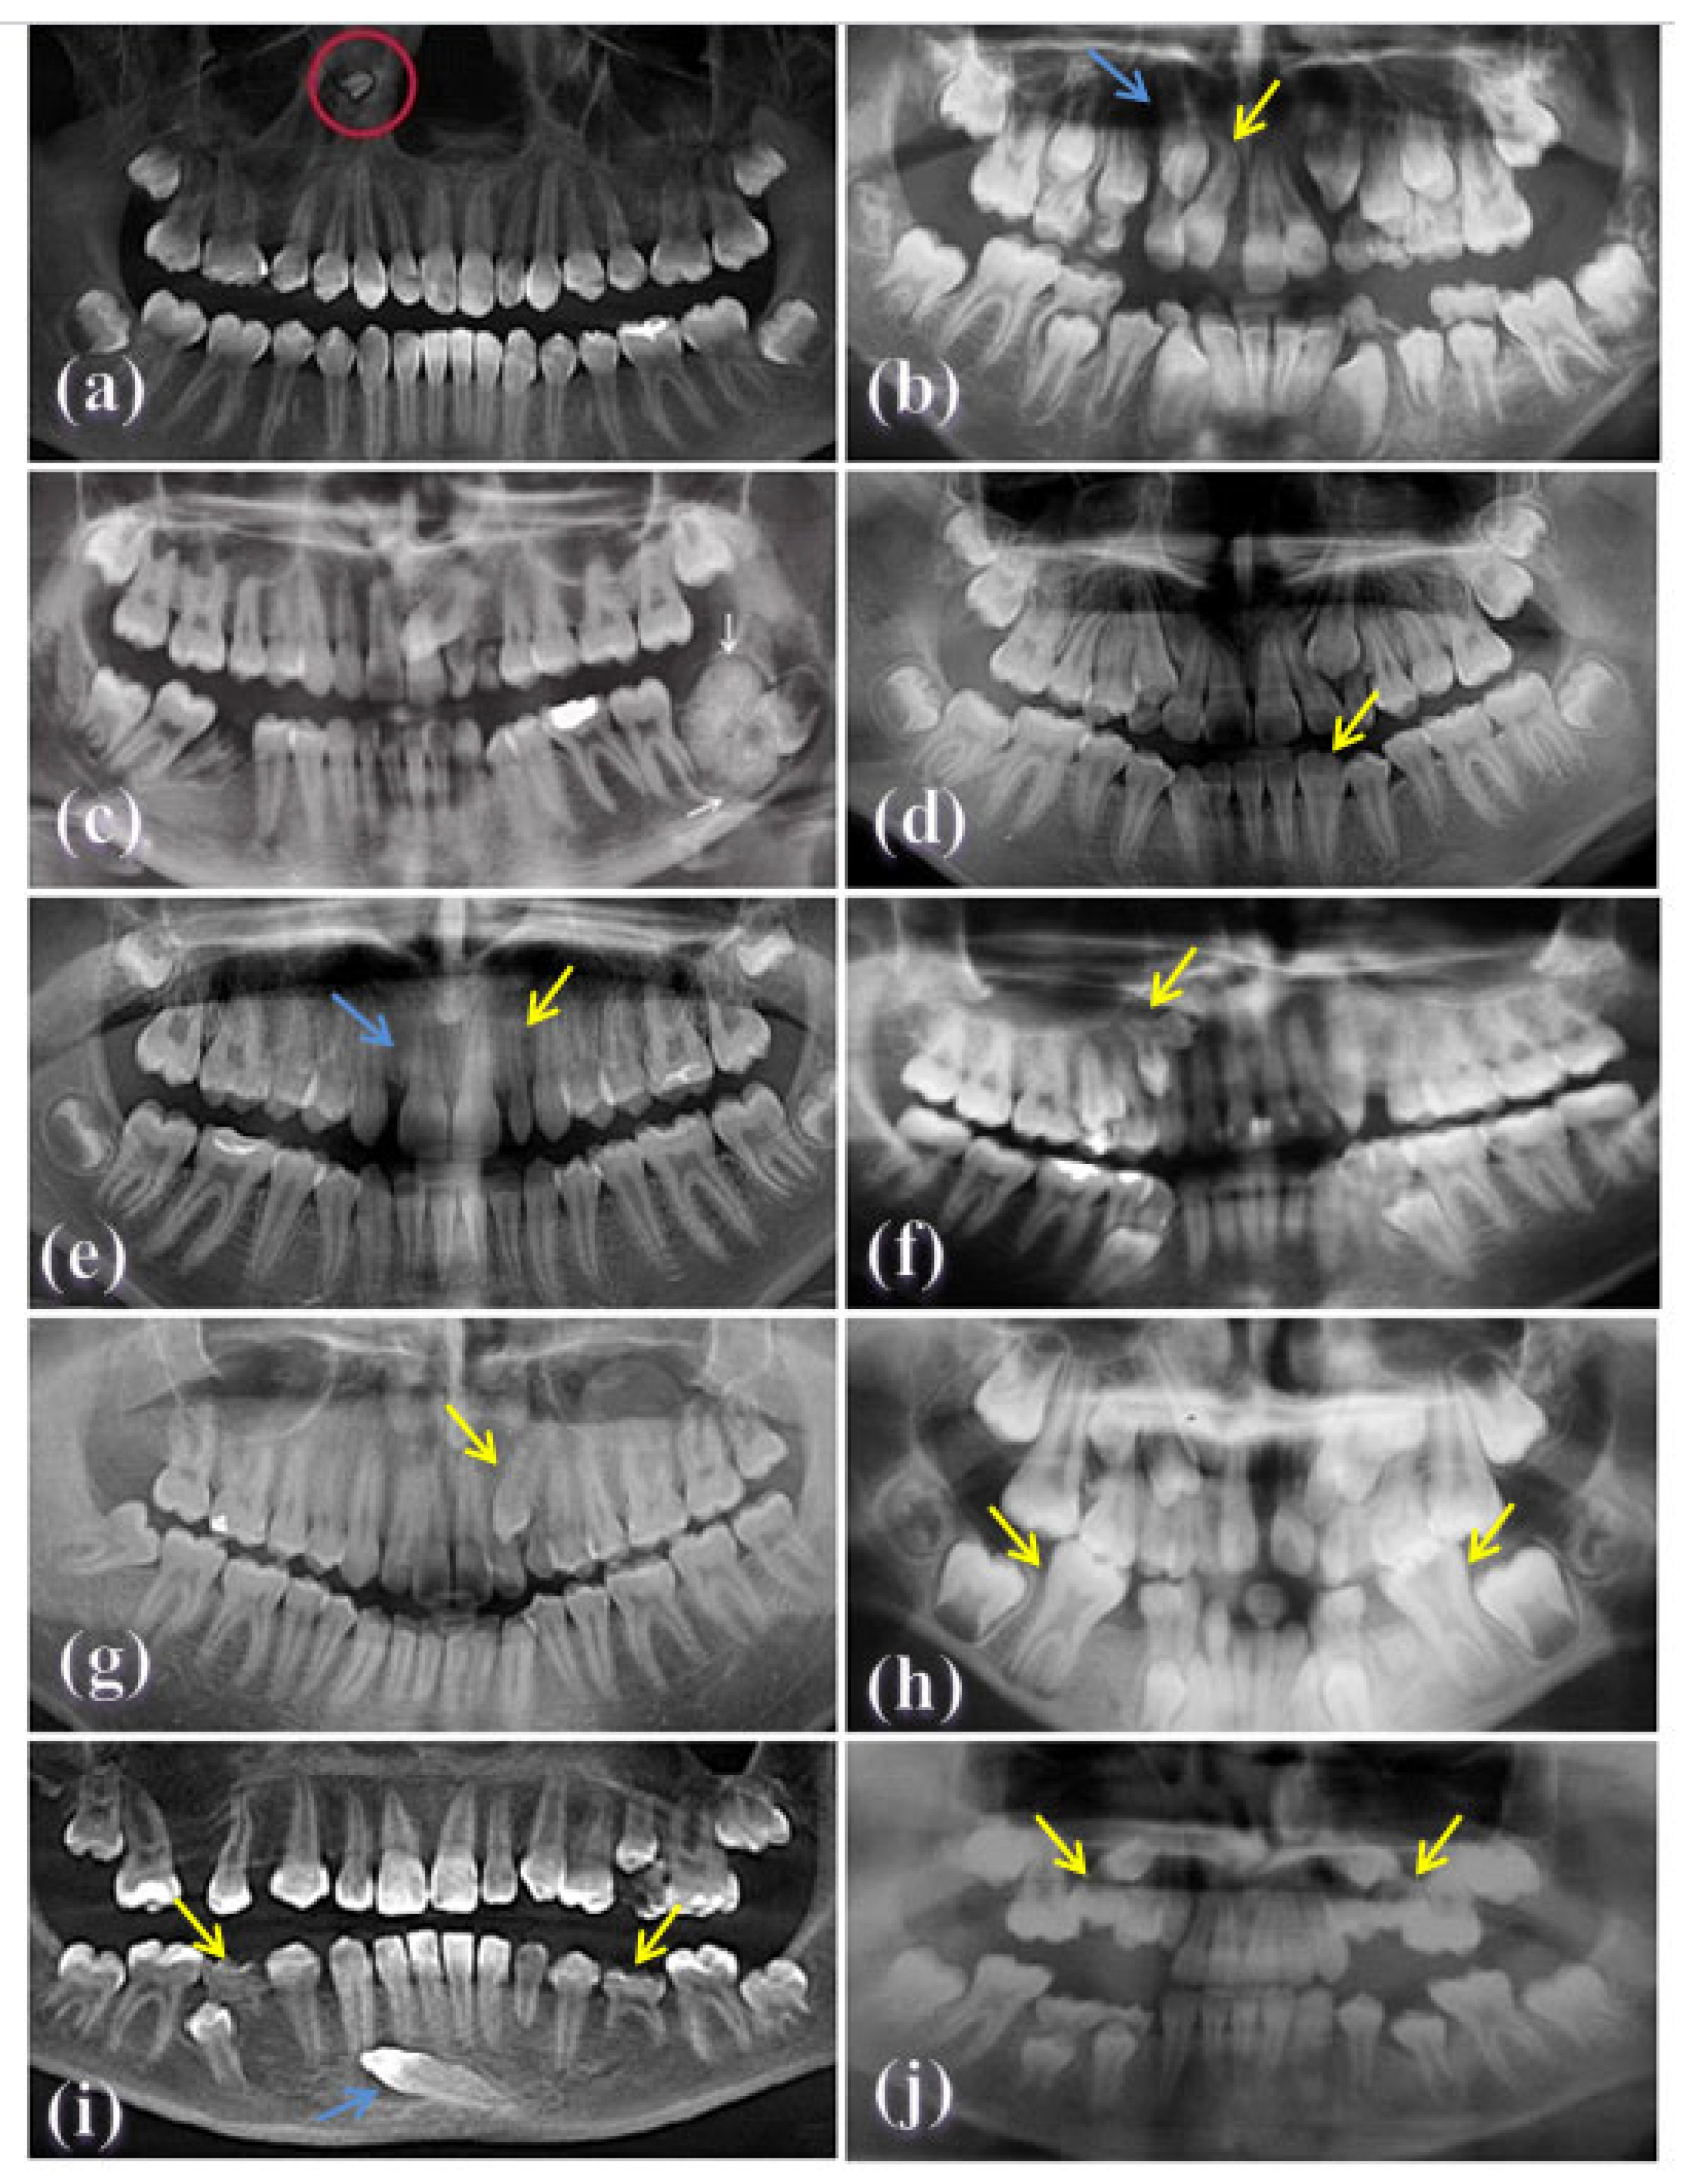

Fourteen dental anomalies were assessed. These anomalies were diagnosed according to the criteria shown in Figure 2, Table 1.

Figure 2. Examples of dental anomalies evaluated on panoramic radiographs: (a) an ectopic supernumerary tooth located at the right maxillary sinus (red circle) (a 16 year-old patient); (b) dilaceration of tooth #11 (yellow arrow), and transposition of the maxillary lateral incisor and canine (blue arrow) (a 12-year-old patient); (c) compound odontoma at the left angle of the mandible (white arrows) (a 21-year-old patient); (d) fusion of teeth #31 and #32 (yellow arrow) (a 14-year-old patient); (e) an example of missing teeth #12 (blue arrow), and a peg shaped toot #12 (yellow arrow) (a 16-year- old patient); (f) gemination (yellow arrow) (a 25-year-old patient); (g) an impacted upper canine #23 (yellow arrow) (a 24-year-old patient); (h) taurodontia of lower first molars (yellow arrows) (a 7-year-old patient); (i) transmigration of the lower canine (blue arrow) and retained teeth #75 and #85 (yellow arrows) (a 13-year-old patient); and (j) subemerged primary upper second molars (yellow arrows) (a 9-year-old patient).